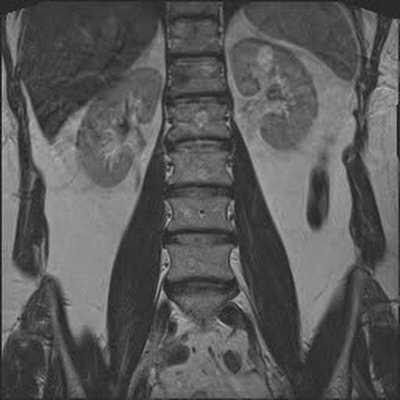

Гемангиомы на снимке МРТ поясничного отдела позвоночника в коронарной проекции

Опухолевое образование (обведено красной линией) на снимке МРТ поясничного отдела в аксиальной проекции